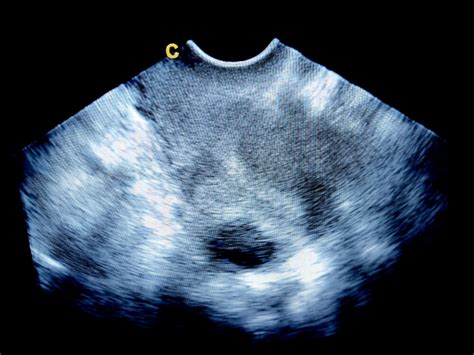

V súvislosti s hodnotami hCG je dôležité spomenúť aj ultrazvukové vyšetrenie. V skorých štádiách tehotenstva, keď hladina hCG dosiahne určitú úroveň, lekár by mal byť schopný vidieť gestačný vak v maternici.

- Pri hodnote hCG okolo 1000-1500 mIU/ml by mal byť viditeľný gestačný vak.

- Pri hodnote hCG okolo 1500-2000 mIU/ml by mal byť viditeľný žĺtkový vak v gestačnom vaku.

- Pri hodnote hCG okolo 5000-7000 mIU/ml by mal byť viditeľný zárodok s akčnou srdcovou činnosťou.

Ak sa tieto nálezy na ultrazvuku nezhodujú s očakávanou hladinou hCG, lekár môže podozrievať na abnormálne tehotenstvo. Napríklad, ak je hladina hCG vysoká (napríklad 1800 mIU/ml), ale na sone je viditeľný iba gestačný vak a nie žĺtkový vak, môže to byť v poriadku, ak sa jedná o veľmi skoré štádium, ale lekár bude situáciu pozorne sledovať. Ak by však na sone nebolo vidno nič, napriek vysokej hladine hCG, mohlo by to signalizovať mimomaternicové tehotenstvo.